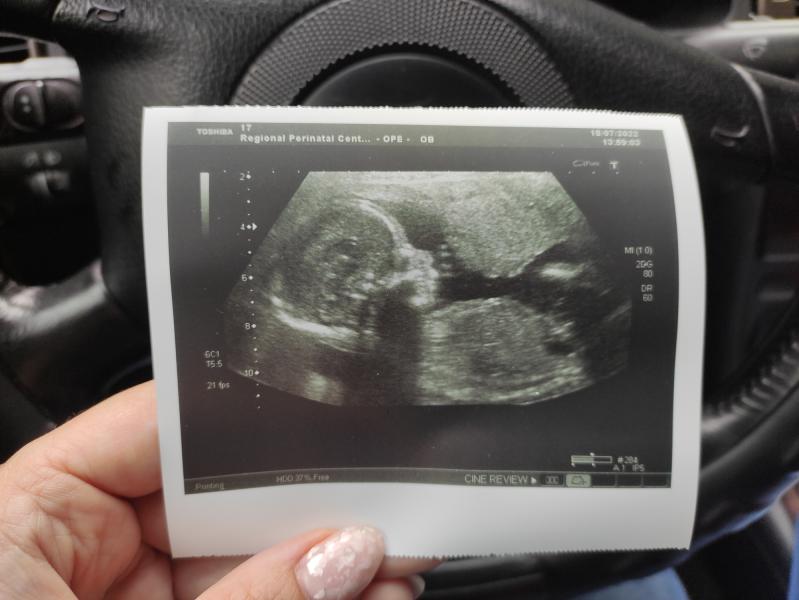

Наши 300 грамм счастья 🥰

Всегда поражаюсь этим "фото" , такие человечки уже и всего 300 грамм 😶 все-таки это удивительно прекрасно 🥰

Ага, и эти 300 грамм такой силой обладают, что лупят изнутри ощутимо 🤣